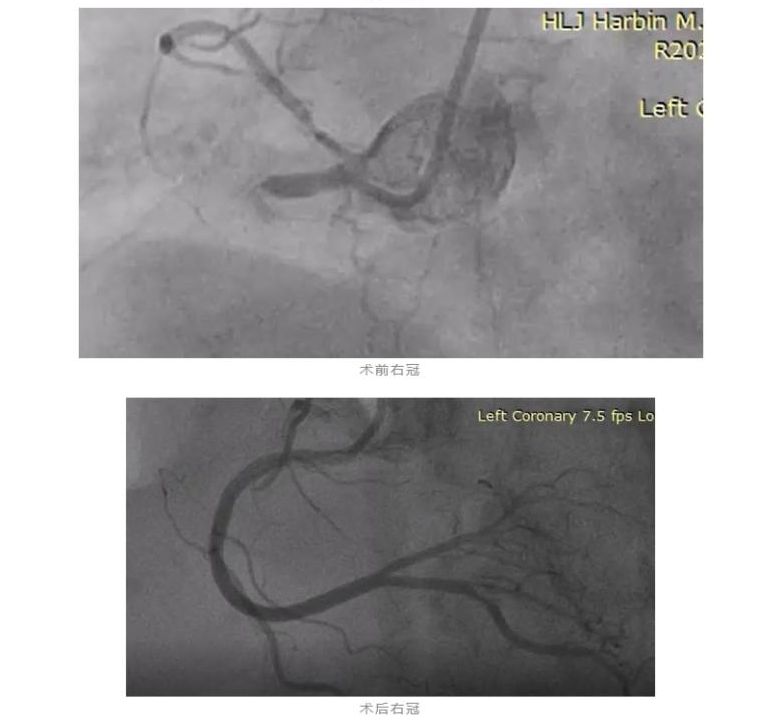

经过评估和准备,医生们先是快速地成功为这位老人开通了一支刚刚闭塞的血管,为患者打开了“生命之门”,使病人的血压能够维持,随后又迅速开通了第二支慢性完全闭塞的病变,心脏得到了血运供应后,老人生命体征逐渐平稳,后续成功开通的第三根慢性闭塞的病变血管,达到了完全的血运重建。